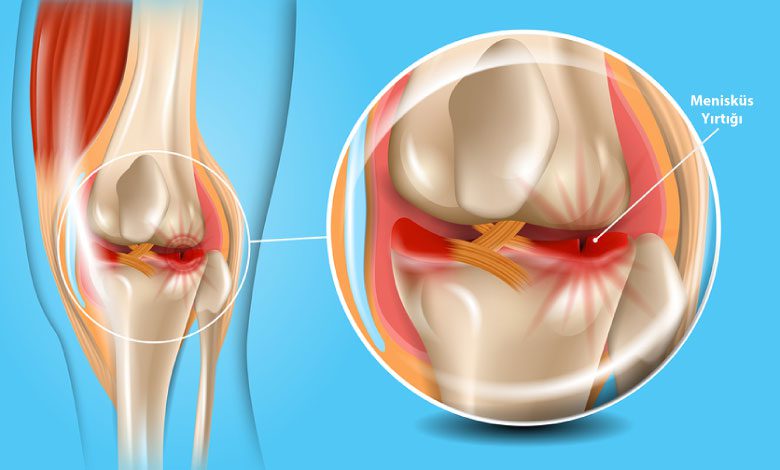

Menisküs, vücutta bulunan femur yani uyluk kemiği ve kaval kemiği arasındaki yastıkçıklara verilen isimdir. Dizlerde iç ve dış kısımda olmak üzere iki tane sert kıkırdak yapısında bulunmaktadır. Genelde düşme, çarpma, travma gibi durumlardan sonra menisküs yırtığı meydana gelmektedir. Menisküs yırtıklarında kişide ağrı ve şişlik görülmektedir. Birçok kişinin başına gelen menisküs yırtılması nedir? Menisküs neden yırtılır? Ne gibi belirtiler gösterir? Aklınıza takılan bu tür soruların yanıtını sizlere özel hazırlamış olduğumuz yazımızın devamında bulabileceksiniz.

Dizlerde en sık meydana gelen kıkırdak yaralanması menisküstür. Menisküs, sürekli hareket halinde olan kemikleri yıpranmaya ve aşınmaya karşı korumaktadır. Bu kadar yararlı bir işleve sahip olan menisküste meydana gelen menisküs yırtığı, bireylerde ciddi ağrılara neden olmaktadır. Bu nedenle dizde yaşanan ağrı durumunda vakit kaybetmeden doktora gidilmesi önerilmektedir. Geç kalındığı zaman yırtık büyüyerek ağrıyı daha da artırmaktadır.

Menisküs Nedir?

Diz ağrısı yaşayan kişilerin akıllarına direkt olarak menisküs yırtılması geldiği için menisküs nedir aktarmak istedik. Genelde spor yapan gençlerde görülen menisküs yırtığı özellikle darbeler nedeniyle meydana gelmektedir. Tedavisi yapılmayan menisküs yırtıkları, sporcuların spor kariyerini bitirebilmektedir. Bu nedenle menisküs yırtığının kesinlikle tedavi edilmesi gerekmektedir.

Menisküs genelde halk arasında bir hastalık olarak bilinmektedir. Ancak menisküs aslında diz bölgesinde bulunan kıkırdaklar korumaya yarayan önemli bir yapıdır. Ancak kaza, düşme, darbe gibi çeşitli nedenlere bağlı olarak menisküste meydana gelen yırtılma asıl rahatsızlıktır. Günlük hayatta birçok kişinin başına gelebilecek menisküs yırtığı ciddi ağrılara neden olduğu için bir an önce tedavi edilmelidir.

Menisküsler dizin iç ve dış kısımlarında olmak üzere iki tanedir. Menisküs yırtıkları da iç menisküs yırtığı ve dış menisküs yırtığı olarak ikiye ayrılmaktadır. Menisküs yırtığı için doktor tarafından ilaç tedavisi, fizik tedavi ve en son cerrahi tedavi yöntemleri uygulanmaktadır. Uygulanan yöntemler ile iç menisküs yırtığı iyileşmektedir. Zaman kaybetmeden doktora gitmenin ve tedaviye erken başlamanın sonuç üzerinde etkisi büyüktür.